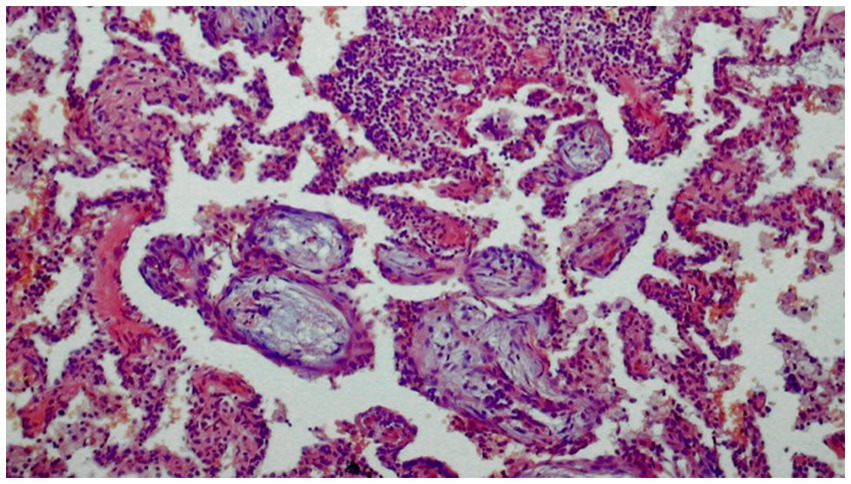

Histological examination

In OP, histological examination detects a rich fibrous exudate in alveolar spaces, which expands into alveolar ducts and respiratory bronchioles; it forms characteristic polypoid lesions accompanied by a polymorphic inflammatory infiltrate composed of macrophages, plasma cells, lymphocytes, and eosinophils (Figure 7).

Figure 7

Histological image of organizing pneumonia (H-E). Alveoli filled with loose tissue forming polypoid formations extending into the respiratory tracts with a small diffuse inflammatory infiltrate in the interalveolar spaces.

Some degree of inflammation is observed in the lung interstitium, but the lung architecture remains intact. The lesions usually have a unilocular appearance; typically, advanced fibrotic changes are not present at the time of diagnosis. OP involves extensive apoptotic activity in the extracellular matrix. The damaged lung is remodeled by re-epithelialization and repair of the basement membrane, along with resorption of the accompanying inflammatory exudate.